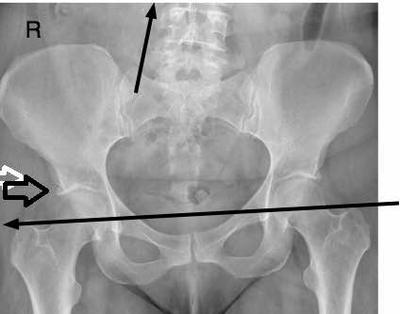

Often there are pre existing conditions in the hip too.

I was in a car accident in 2009 I was in the passenger seat and had my right leg tightened against the wheel well as I was setting the papers for my new car on the floor, a few blocks away from the dealership, wham. 90mph impact into this wheel well. I can no longer pull my leg to my chest and my leg falls outward/way from body.

An MRI of my back shows "the back of a person much younger" minus one spot in my mid back of "little concern". The doctors "didn't want to get involved", so claimed all my symptoms were MS (I was incredibly active before this accident). I am in my mid 40s. I moved out of that town after "settlement" in 2014. In 2015, I had two hours worth of ortho surgery to my right knee (every tendon and ligament was broken or ruptured minus the medial); have arthritis in my hip and knee.

I have been told that my femoral nerve is trapped, but they can't figure out where; MRI doesn't show it. Meanwhile my thigh muscles are disappearing. The Ortho surgeon just gave me a steroid injection in my knee for arthritis and is talking about sending me to another state for the paralysis as my area doesn't have the expertise and testing. Any suggestions? I can send copies of MRIs if you need them.

Since you are unable to pull your knee to your chest, this looks like a classic hip condition to me; there could be a femoral nerve problem but in the absence of back pain, and radiating pain to your leg when bending in various directions, my thoughts are directed to your hip.